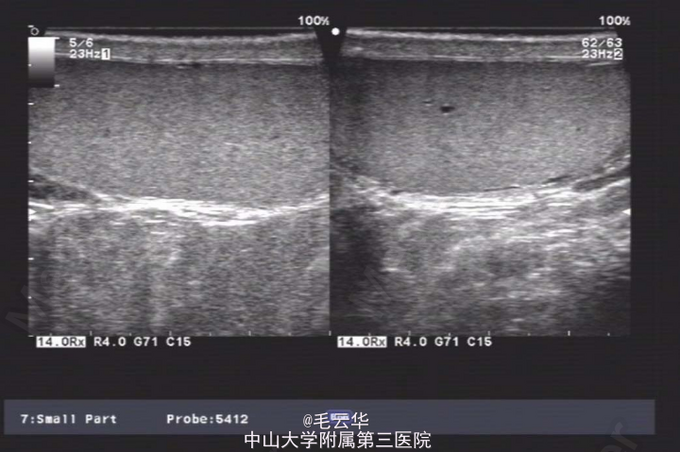

双肾区无红肿、隆起,无叩痛,双侧肋脊点、肋腰点无压痛。腹平软,双侧上中输尿管点无压痛,膀胱区无压痛。双侧腹股沟区未触及肿物,尿道外口未见异常,阴囊无水肿,双睾丸可触及,肛周皮肤无红肿。盆腔MR提示:双侧精囊腺体积缩小(未见片)。彩超提示:右侧输精管、精囊缺如可能;双侧睾丸偏大,附睾小管扩张;前列腺囊肿。精液常规提示精液量少,离心后无精子。

入院诊断:无精症查因。 入院完善术前相关检查,射精管切开+输精管探查术。麻醉成功后,取截石位,常规消毒铺巾,连接好4.5/6.5F输尿管硬镜和监视系统。经尿道进镜入膀胱,见双侧输尿管开口裂隙状,膀胱内未见异常。尿道未见明显异常,精阜稍隆起。镜下未找到双侧射精管开口,硬膜外导管引导进镜入前列腺小囊,见囊腔狭小,囊壁炎性增厚,囊内未见射精管开口,考虑射精管口梗阻,遂换用电切镜,切除部分精阜,切开双侧射精管口,再用硬膜外导管引导输尿管硬镜入射精管,进入困难,结合病史及影像学检查,提示射精管发育不良并梗阻。作双侧阴囊切口,逐层切开,游离出睾丸和精索,探查双侧输精管,见左侧输精管呈纤维条索状,未见管腔结构,右侧未见输精管,考虑为先天缺如,遂行双侧睾丸活检,术野予以止血,逐层缝合切口,术毕。手术过程顺利,麻醉效果满意,术中无出血,术后安返病房。